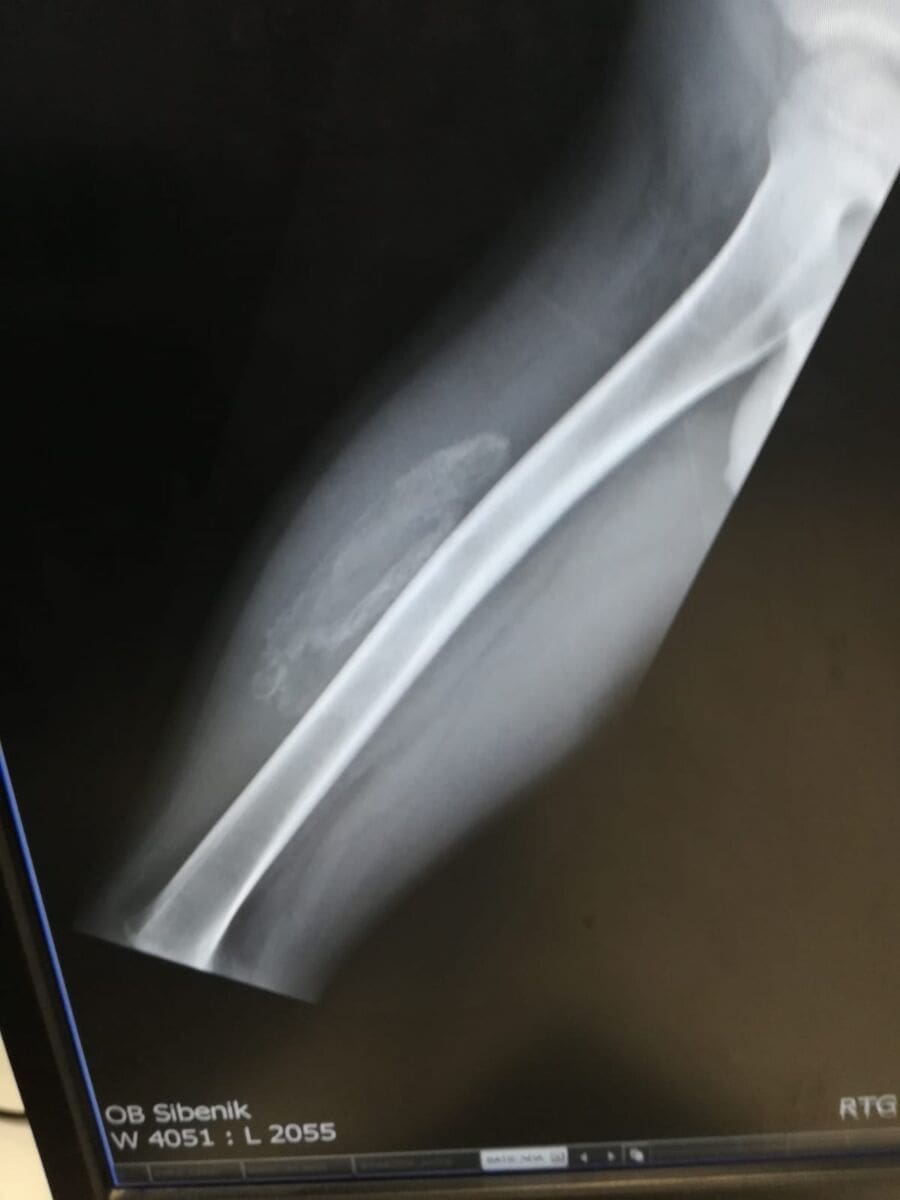

Po pisanju medija, učenika je ozlijedio školski vršnjak, pri čemu mu je puknuo mišić na nozi, a škola nije reagirala na odgovarajući način, sve dok majka ozljeđenog učenika nije incident prijavila nadležnom ministarstvu.